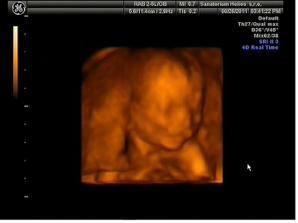

26.8.11 Emicka je uzasna🙂)) cca 25cm, 327g, mame fotecku i dvd, krasne se hybala,. zivala.. no nadhera🙂